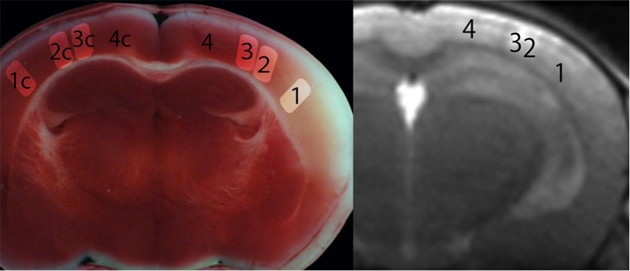

(図1)撮影した画像と実際の脳の状態の比較

発症24時間後のマウス脳の断面(左画像)では、壊死した部分は白く、壊死を免れた部分は赤くなっている。右画像は虚血性ストレス後の急性期に撮られたT2信号強調画像(血管性浮腫の部位が白く描出されている)。

左に示した発症24時間後の脳を用いた組織学的診断によって、以下のことが確認され、それによって各ROIが定義された。

1(ROI-1)は、虚血性ストレスが最も強く、虚血発症直後に殆どの細胞が死滅する領域

2(ROI-2)は、虚血性ストレスが中等度で、24時間以内に大多数の細胞が死滅する領域。

3(ROI-3)は、虚血性ストレスが軽度で、24時間後には大多数の細胞が生存する領域。

4(ROI-4)は、虚血性ストレスがかからなかった、無傷の領域。

※ROI(関心領域)測定法:特定の解剖学的部位に特化した分析方法。